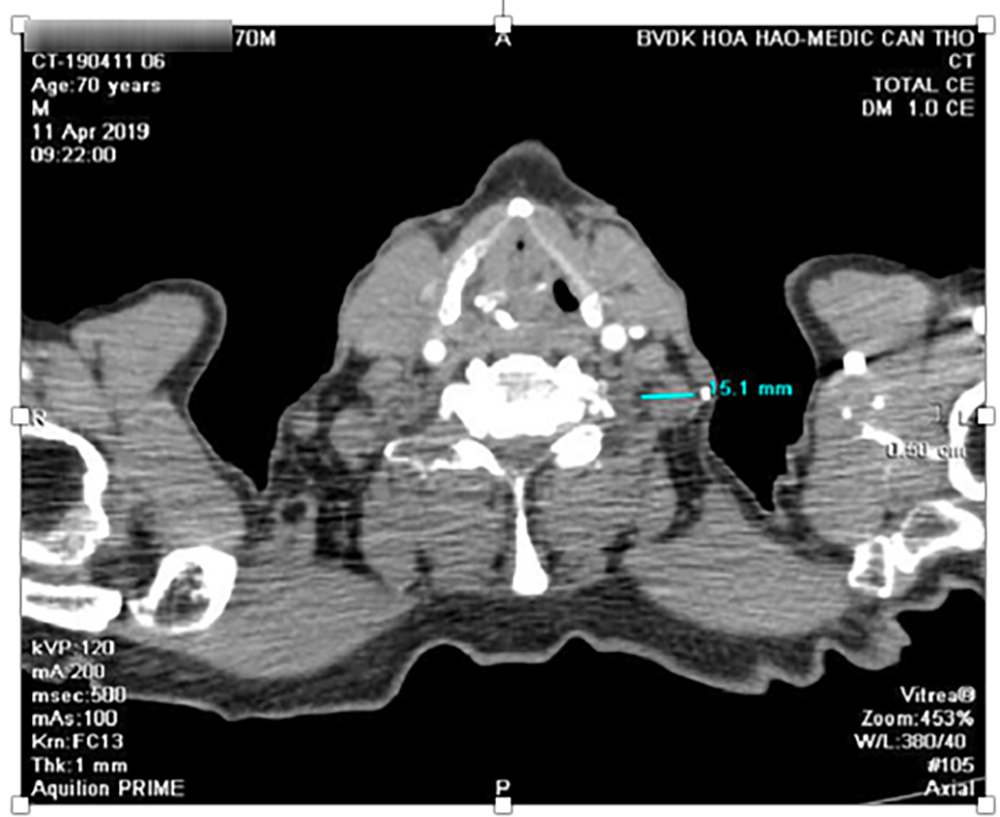

Hạch dạng di căn 12mm vùng thượng đòn trái.

Hạch 14mm vùng thượng đòn trái